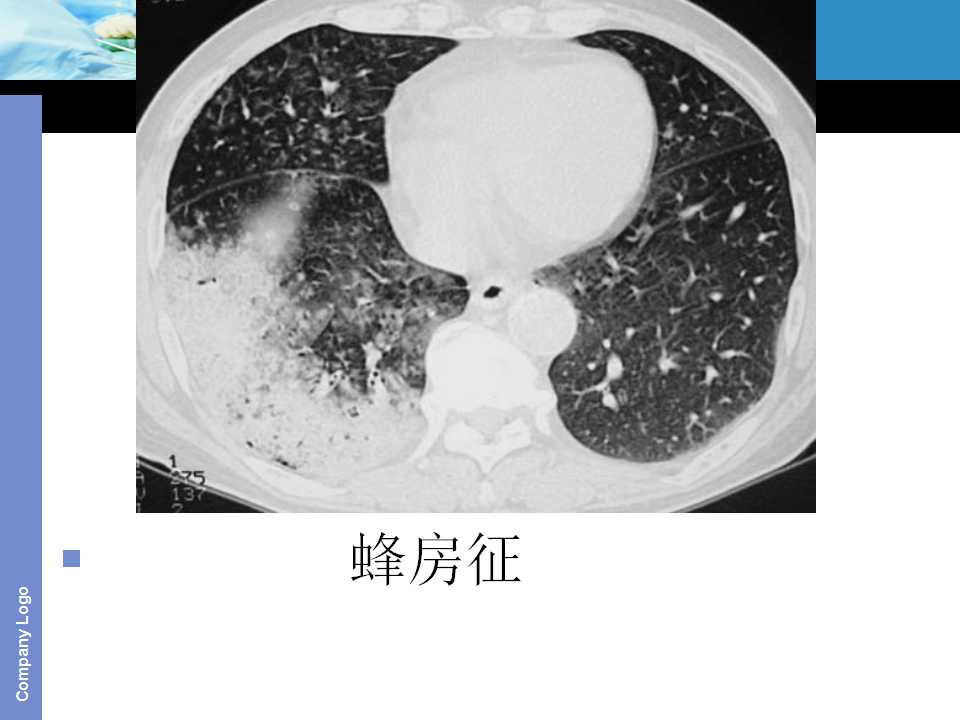

肺癌影像诊断